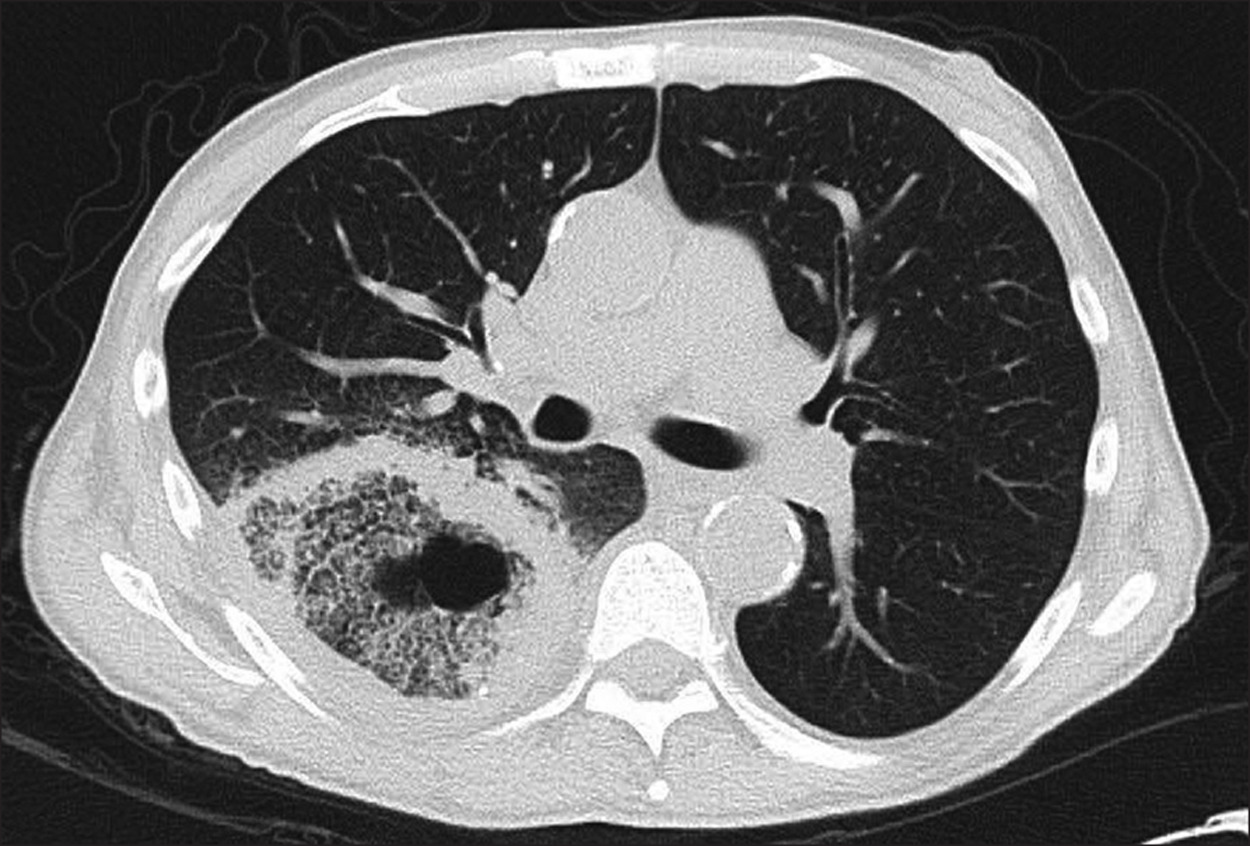

Het onderzoek voor pulmonale IA dat de voorkeur heeft is een hoge resolutie CT-thorax3,5. Bij neutropene patiënten kunnen hier de klassieke beelden gezien worden van dense, welomschreven nodules, al dan niet met omliggend matglas (het zogeheten “halo sign”, wat wijst op angio-invasie en invasie door reactieve leukocyten), “air-crescent sign” waarbij een luchtsikkel zichtbaar is rondom een fungale bal (compatibel met laattijdige infectie), en meer uitgebreide consolidaties27. Deze tekens zijn echter niet uniek voor IA, en kunnen evengoed gezien worden bij andere fungale of bacteriële infecties, evenals bij auto-immune of maligne processen28.

Omgekeerd haloteken bij mucormycosis

Overgenomen uit: Wang et al. Clinical diagnostic value of spiral CT in invasive pulmonary fungal infection. Exp Ther Med. 2019;17(5):4149-4153.